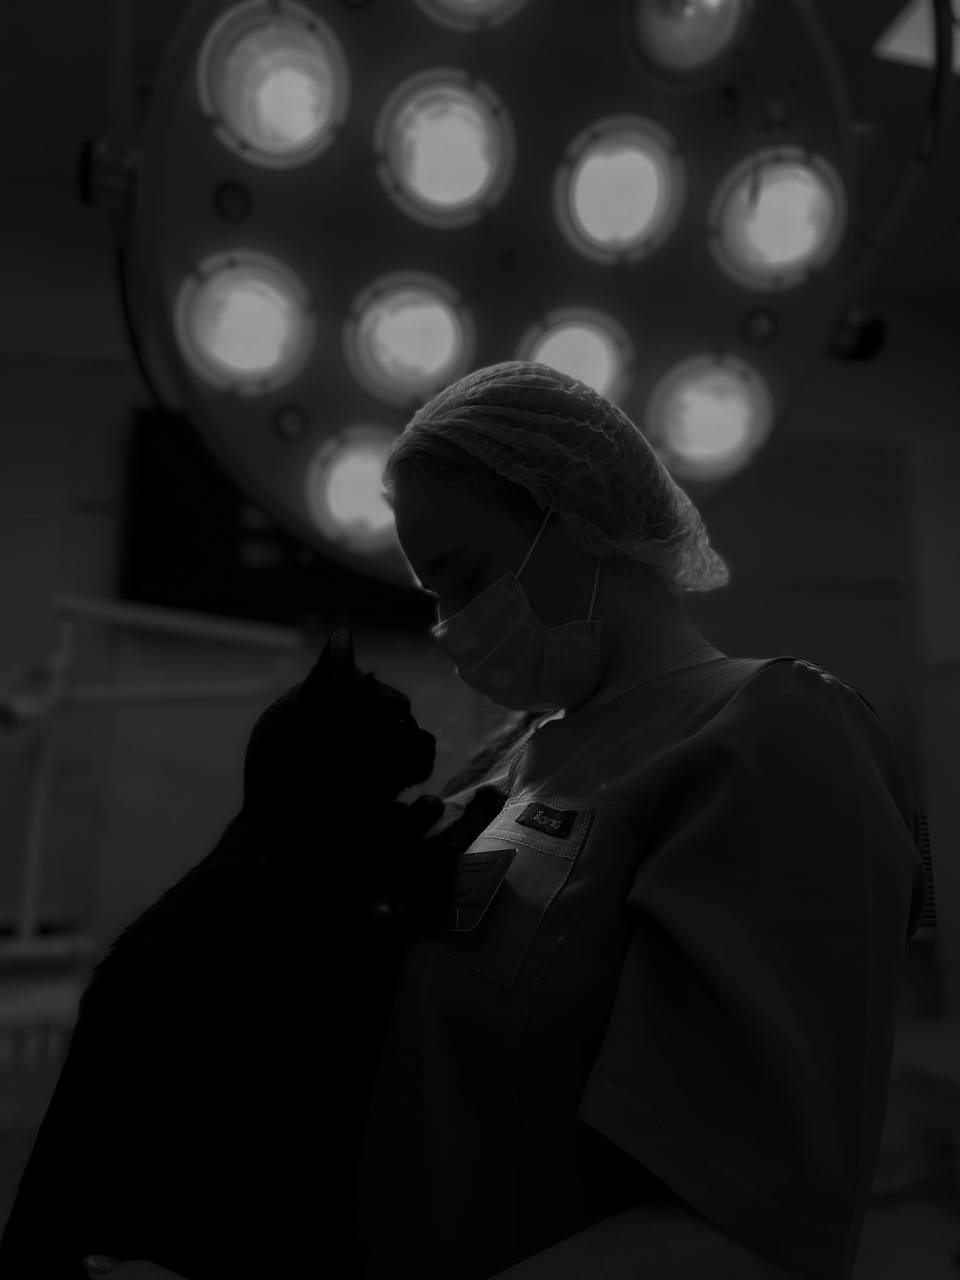

- Хирургия

- Анестезиология и интенсивная терапия

Кастрация кошек и собак